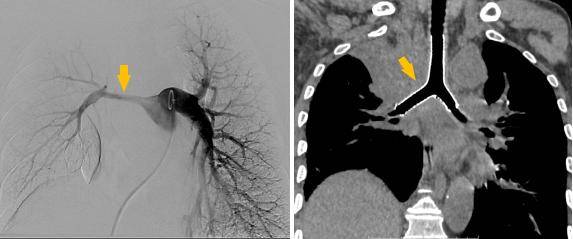

术前受压变窄的右肺动脉和中央气道

同期置入支架后狭窄明显改善